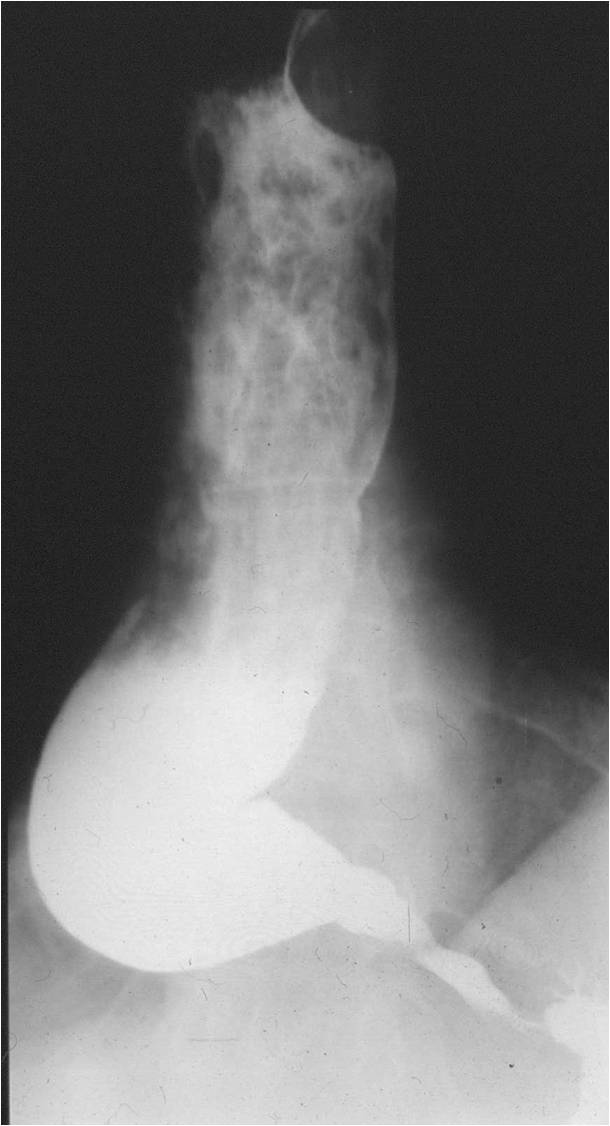

Image

Fig.2.: Achalasia

Radiographic findings: marked dilatation of the esophageal lumen. Luminal diameter can be seriously widened. In advanced cases the tortuous gullet constitutes the mediastinal interface. The cardia shows conical narrowing. The esophageal lumen is filled with undigested food. Opening of the cardia is delayed, emptying is intermittent. The stomach is shrunken. The result is a so called microgaster as the esophagus takes over the stomach’s reservoir function.